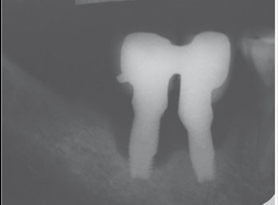

Radiographic examination. All authors agree on the importance of radiographic examination of implants over time. The main disagreement was on when the initial x-ray should be taken: when the implant is placed, when the restoration is placed or after bone remodeling. This workshop found greater scientific evidence, as well as agreement among authors, supporting initial radiographic examination, after post-restoration bone remodeling11,13,14.